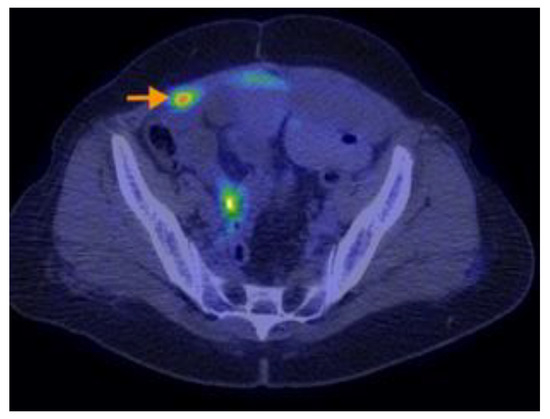

3.2.3. Imaging Findings, Diagnosis, and Differential Diagnosis